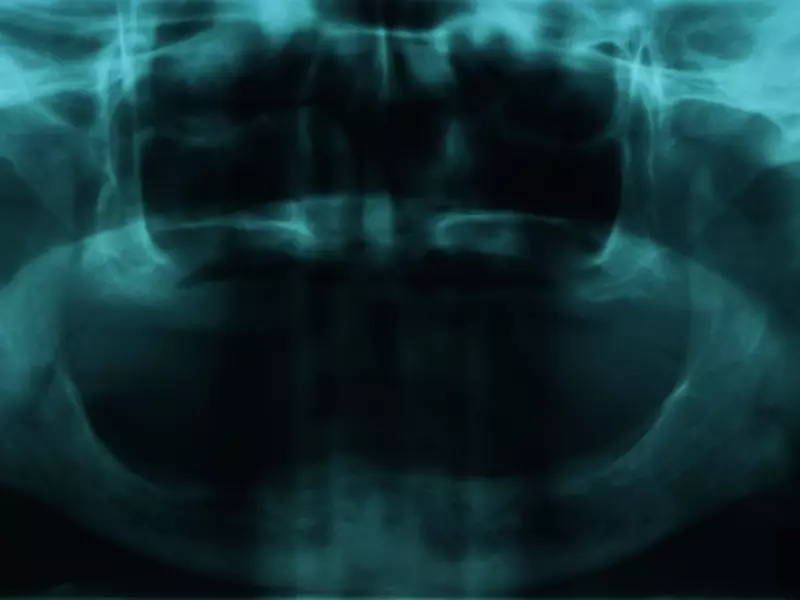

Doktor Attilio Bedendo omówił szczegółowo, krok po kroku, technikę protetyczną VertPrep, dzięki której możliwa jest rehabilitacja periodontologiczno-protetyczna. Ten proces leczenia protetycznego wymaga jednak cierpliwości, bowiem obejmuje fazy długoczasowego korzystania z tymczasowych uzupełnień i przeplatany jest fazami leczenia periodontologicznego, w tym chirurgicznego. Pozwala jednak na uzyskanie właściwej okluzji, a oddana pacjentowi konstrukcja jest funkcjonalna i estetyczna oraz umożliwia prawidłowe utrzymanie higieny.